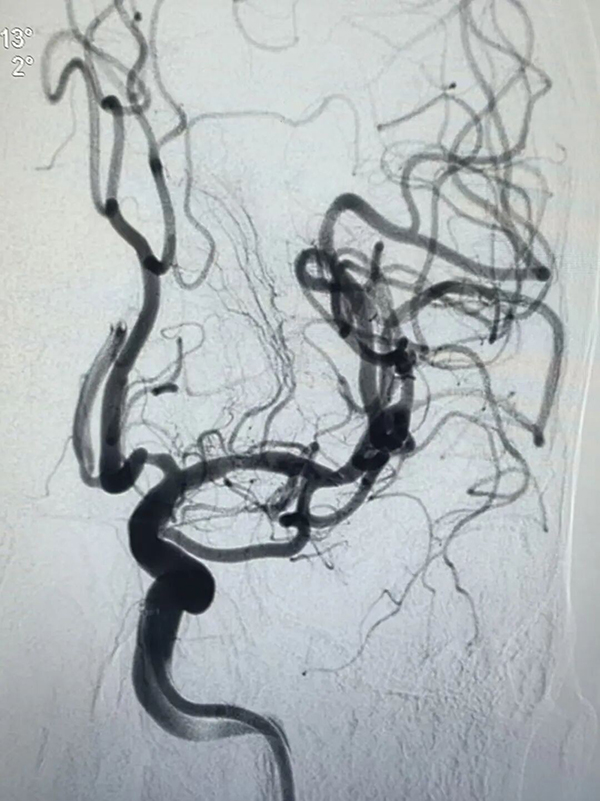

北院神经外一科副主任医师王伟君接诊后,第一时间为陈女士完善头部CT检查,结果提示“脑沟内可见血管高密度症”,病情已迫在眉睫。王伟君当机立断,先为患者实施了全脑血管造影检查。造影结果清晰显示,患者双侧大脑中动脉均存在狭窄病变,其中右侧大脑中动脉M1段重度狭窄、管腔近乎闭塞,血流淤滞严重,这正是引发急性脑梗死的“责任血管”,已达到紧急干预指征。

此次右侧大脑中动脉球囊扩张支架成形术难度极高、挑战严峻:一方面,颅内生理空间狭窄,解剖结构错综复杂;加之右侧大脑中动脉M1段重度狭窄区域,紧邻关键神经与重要血管,术中可操作空间极其有限,术者每一步操作都需做到极致精准,稍有偏差便可能引发血管破裂、血栓脱落等致命并发症。另一方面,患者同时合并左侧大脑动脉狭窄,病情呈双侧受累特点,需统筹兼顾两侧病变,科学规划术区布局,为后续治疗预留充足操作空间,对术者的专业技术、临场心态与手术耐力均是极大的考验。

术中,手术团队精准操控微球囊导管,顺利穿越狭窄病变区域,缓慢充盈扩张球囊,逐步疏通闭塞血管管腔;随后精准植入支架,牢固贴合支撑血管壁,顺利疏通血管“堵点”,为脑部血流畅通搭建起稳固高效的生命通道。手术全程,医护人员全程严密监测患者生命体征与脑组织灌注状态,每一项操作均精准规范、稳妥推进。